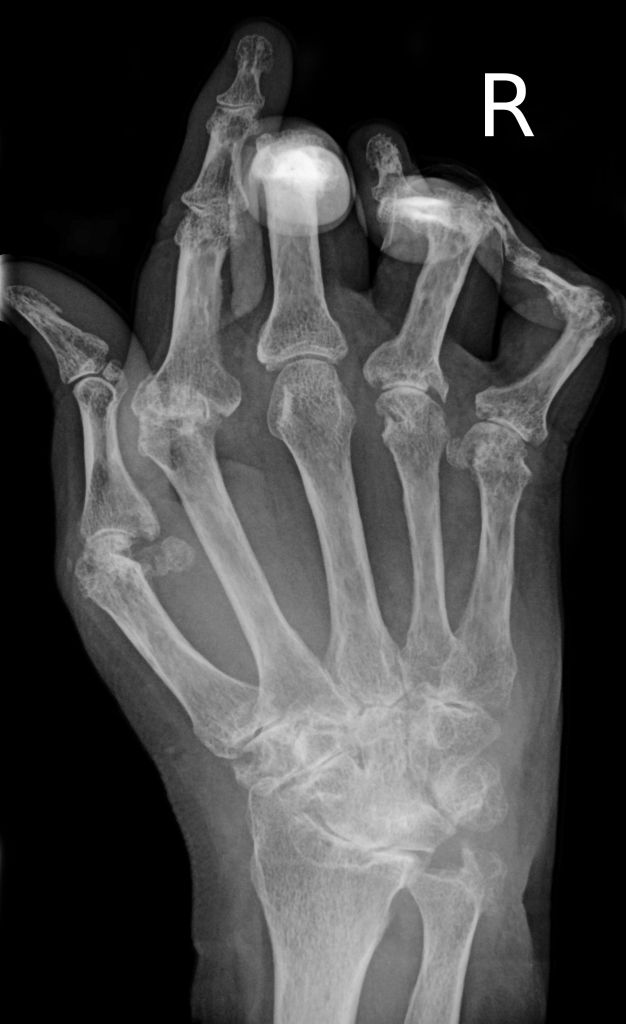

達到治療目標跟沒有達到治療目標會有什麼影響?當然有影響,否則許醫師不會這麼要求,因為醫學研究顯示,任何一個腫起來的類風濕性關節炎都會慢性侵蝕骨頭,讓骨頭像蛀牙一樣崩壞。長期來說,治療沒有達到目標的類風濕性關節炎患者,未來出現骨頭侵蝕與變形的機會與控制最佳的病人相比高很多,使用藥物強度也高很多。也就是說,如果不把病人控制到最佳目標或是次等目標,病人以為自己已經改善很好了,但是過了幾年後照片子發現,骨頭已經慢慢壞掉了。

治療沒有達標的類風濕性關節炎患者未來出現慢性骨頭侵蝕的機會比較高,關節變形的機會也比較高。

在許醫師團隊照顧下的類風濕性關節炎病人,至少每三個月做一次治療達標的評估,至少每年一次手部的X光檢查骨頭侵蝕的情況。同時許醫師也追蹤病人的骨質疏鬆問題、心臟血管問題、膽固醇、血壓、血脂的三高問題,顧好病人的全身系統問題,才不會只顧了關節,病人還是不健康。